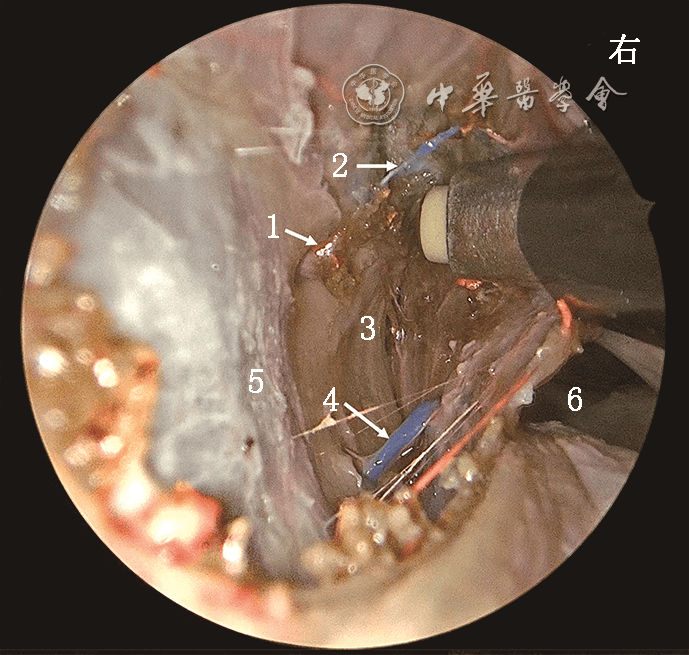

短篇论著 | 带蒂鼻中隔黏膜瓣静脉系统的解剖学研究及其在鼻颅底修复